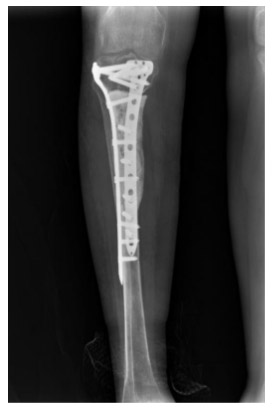

Post-surgery: The X-ray shows that after tumor removal, the resulting cavity was filled with bone cement and reinforced with two anatomical plates.